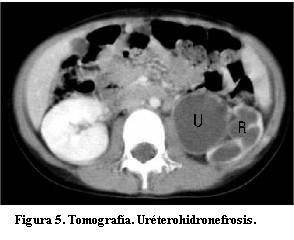

Marcada uréterohidronefrosis izquierda; el parénquima del riñón izquierdo presenta escaso espesor y las cavidades pielocaliciales dilatadas (figuras 3, 4 y 5), con uréter tortuoso en todos sus sectores (figura 6), el cual se afina abruptamente en el sector prevesical inmediato. En el uréter no se observa litiasis de alta densidad, ni compresiones extrínsecas. Riñón derecho sin alteraciones. La vejiga no presenta alteraciones en la pared ni en el contenido. No hay adenomegalias en los territorios estudiados. Hígado, bazo y páncreas sin particularidades. No hay ascitis.